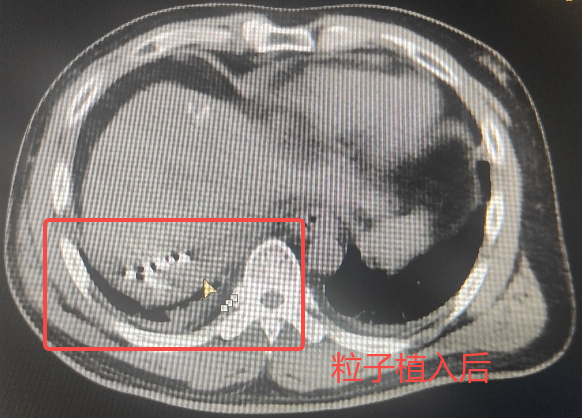

術(shù)中針對小王39mm×30mm的腫瘤,戈偉主任團隊運用先進的治療計劃系統(tǒng)(TPS),通過精密計算,將40顆碘125(I125)粒子部署在腫瘤組織。同時為患者佩戴電磁感應(yīng)胸帶,實時監(jiān)測呼吸波形,精準捕捉每次呼吸周期中約0.3秒的“平靜期”,嚴格限制穿刺和粒子釋放的所有關(guān)鍵操作都在這個瞬間完成,最大程度保護毗鄰的脆弱器官。手術(shù)過程非常順利,術(shù)后小王恢復(fù)良好,目前已順利康復(fù)出院。